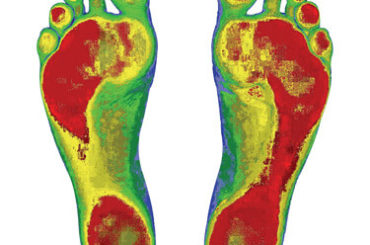

Orthotics

Your feet are your foundation. And structural imbalances in your feet can lead to issues throughout the body.